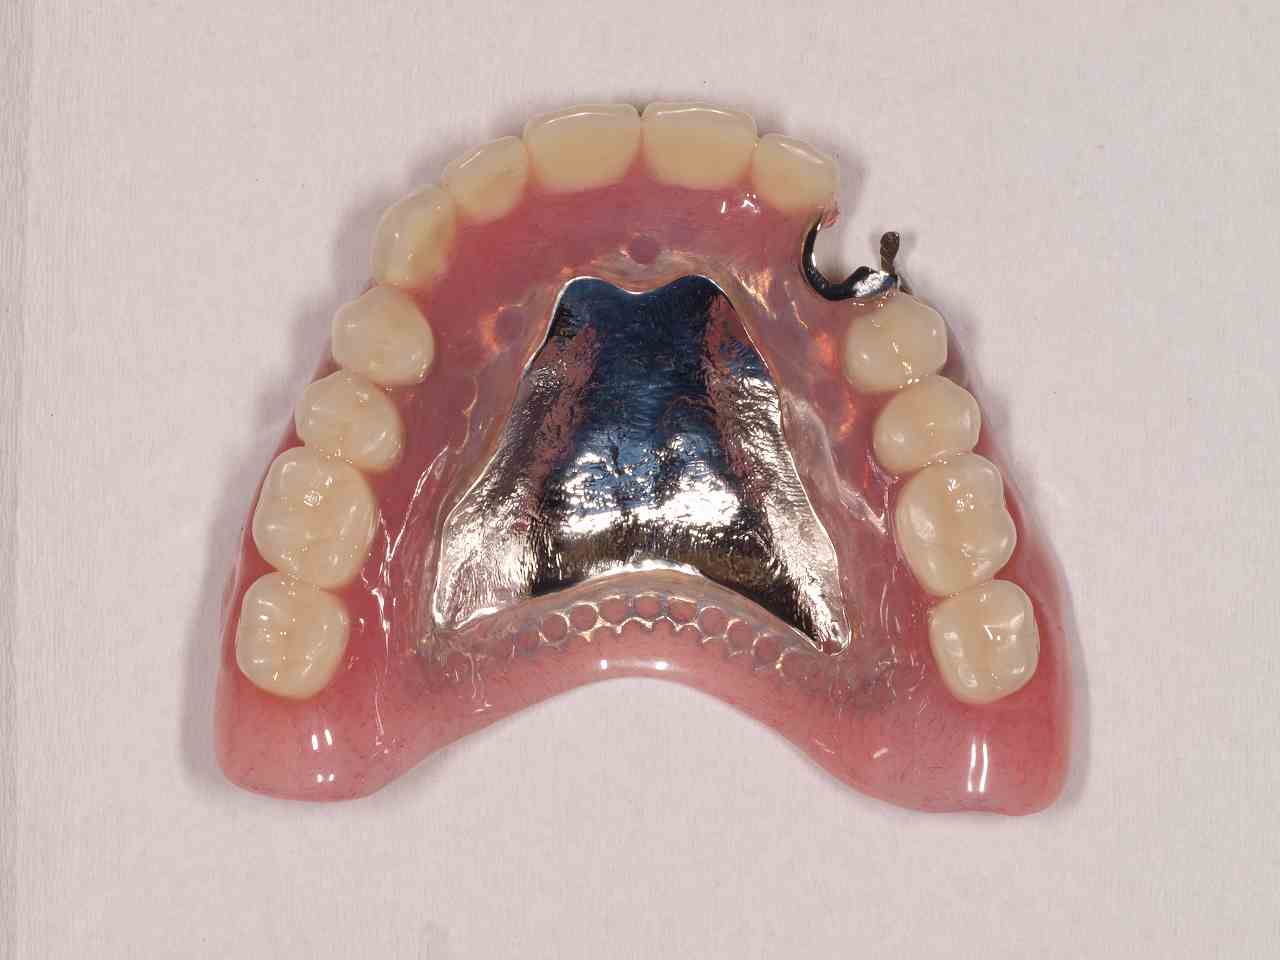

自由診療の入れ歯 上顎は金属床 下顎は柔らかいシリコンを貼り付けた快適な入れ歯|お知らせ |広島市安佐南区の歯科医院 自由診療の入れ歯 上顎は金属床 下顎は柔らかいシリコンを貼り付けた快適な入れ歯 トップ お知らせ・ブログ お知らせ 自由診療の入れ歯 上顎は金属床 下顎は柔らかいシリコンを貼り付けた快適な入れ歯 自由診療の入れ歯 上顎は金属床 下顎は柔らかいシリコンを貼り付けた快適な入れ歯 上顎正面観 2本だけ歯が残っています 右上は弱くなっているためコーヌスにて作成 問題は下顎です 顎堤の高さがなく入れ歯の安定が悪そうです 上顎の金属床 顎堤が吸収した時のためにも公演はレジンにしています 下顎の入れ歯 顎舌骨筋のアンダーカットまでシリコンが維持のために行くようになっています このような外形です Web診療予約 初めての方へ 選ばれ続ける理由 院内設備について 歯が痛いしみる一般歯科 歯がぐらぐらする歯周病 健康な歯を保ちたい予防歯科 子供の虫歯予防をしたい小児歯科 銀歯をセラミックに審美歯科 白い歯を目指しませんか?ホワイトニング 矯正専門医がいるので安心矯正歯科 抜けた歯を補いたいインプラント・入れ歯 医院案内 スタッフ紹介 メリィハウス歯科クリニックオフィシャルホームページ ラベンダー歯科クリニックオフィシャルホームページ お知らせ・ブログ ホーム 診療科目 一般歯科 歯周病治療 予防治療 小児歯科 審美治療 ホワイトニング 矯正歯科 入れ歯・インプラント マウスピース矯正 初めての方へ 院長・スタッフ 設備紹介 医院案内・アクセス メニューを閉じる